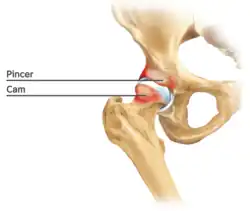

Cam-type femoroacetabular impingement

Cam impingement is created by the abnormal development of the femoral head-neck junction causing what has previously been described as a 'pistol-grip deformity'. This type of deformity is characterised by varying amounts of abnormal bone on the anterior and superior femoral neck at the head-neck junction (see fig. 6). The head-neck junction is at the base of the ball of the hip, where it joins the short neck, which in turn carries on downwards into the femur, or thighbone, itself. A bony protrusion or bump at the head-neck junction has been likened to a cam, an eccentric part of a rotating device. This leads to joint damage as a result of the non-spherical femoral head being forced into the acetabulum mainly with flexion and/or internal rotation. This may impart compression and shear forces to the articular cartilage, and may lead to labral tears and peeling away of the articular cartilage from the underlying bone, so-called cartilage delamination (see fig. 8).[9][10]

Pincer-type femoroacetabular impingement

In contrast, pincer impingement is a result of an abnormality on the acetabular side of the hip joint.[2] The acetabulum may either have a more posterior orientation than normal, otherwise known as acetabular retroversion (seen as the crossover sign on AP radiographs), or there may be extra bone around the rim. This results in contact of the femoral neck against the labrum and rim of the acetabulum during hip movement earlier than might otherwise be the case. Repeated contact between the femoral neck and the edge of the acetabulum may lead to damage to the labrum and adjacent articular cartilage. Bone formation, or ossification within the labrum may be commonly seen as a result of this repeated contact. It is thought that this type of impingement may also predispose to the development of osteoarthritis.

The goal of the arthroscopic treatment of pincer impingement is to reduce the acetabular over coverage of the hip. Methods to reduce this over coverage of the ball by the socket include labral detachment or peel back, acetabular rim trimming using burrs, often reattaching the labrum with anchors at the end of the procedure. With the exception of cases of severe global over coverage of the hip, or situations in which the existing labrum has turned to bone (or ossified), excessive acetabular rim resection should be avoided in order to prevent iatrogenic increases in hip joint contact pressures.[14]